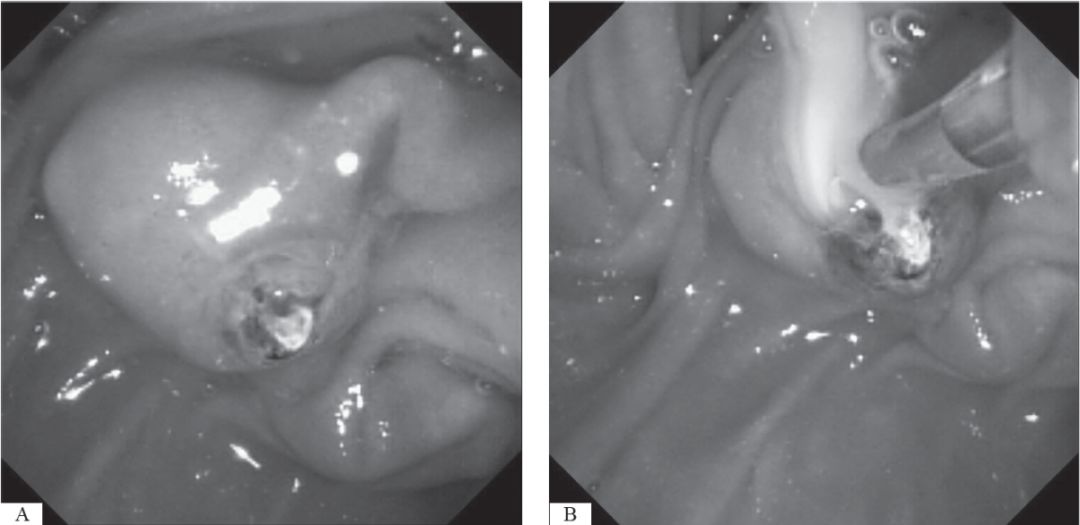

如果结石嵌顿于乳头处,使用针刀进行乳头预切开术更优于传统的内镜括约肌切开术,因在此种情况下,胆道内置管常难度较大(图33-2)。

图33-2 内镜下见结石嵌顿于十二指肠乳头处

A.胆道嵌顿结石,在这种情况下针刀乳头切开术宜为优选;B. 经胆道针刀切开十二指肠乳头后见白色脓汁流出